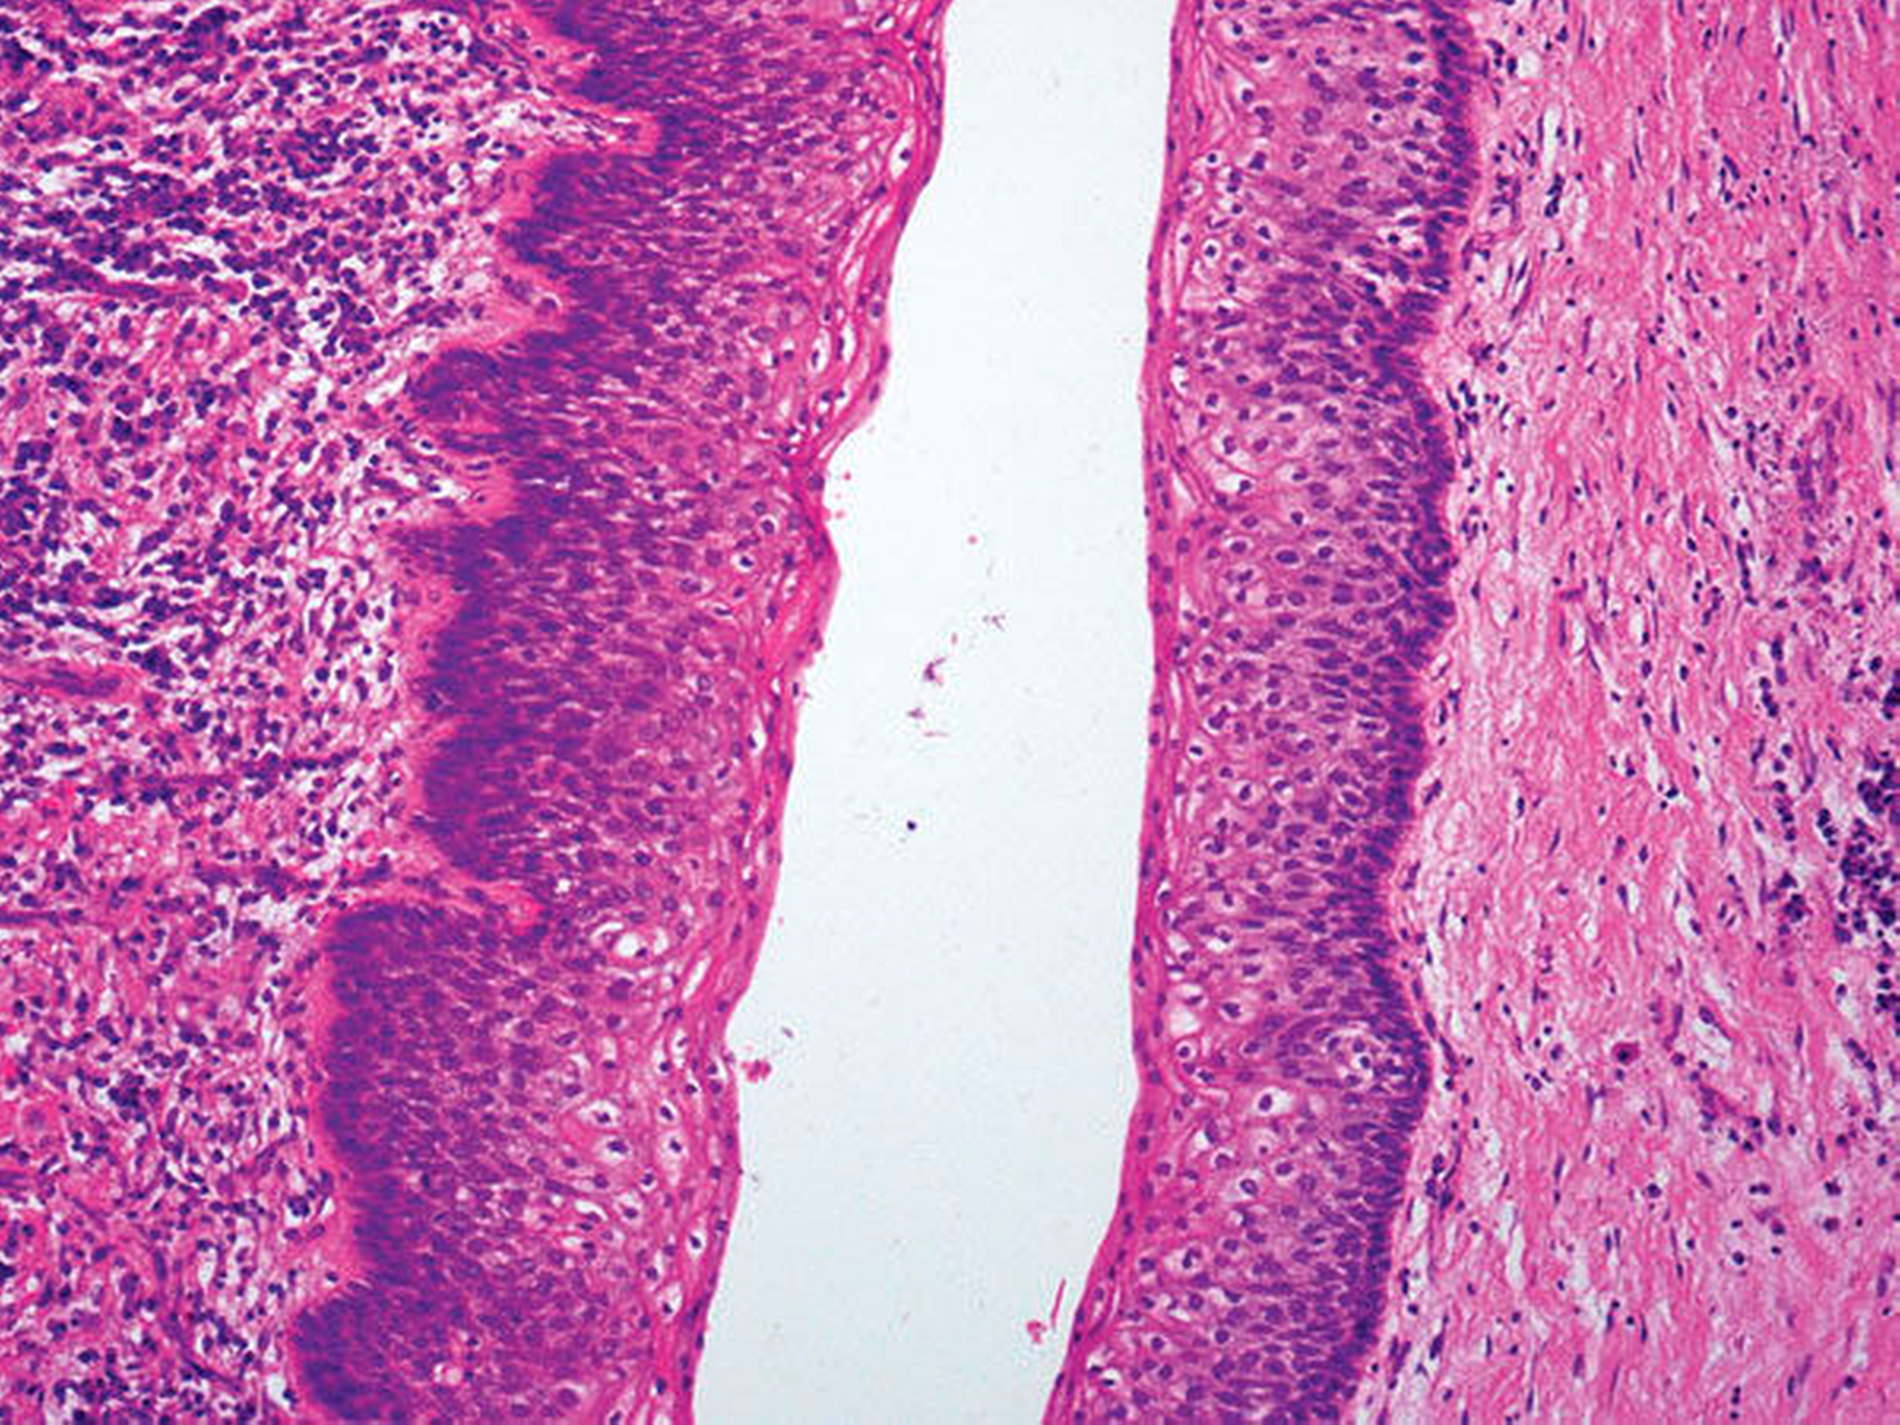

Der weitere Verlauf gestaltete sich komplikationslos, so dass die Patientin nach einem dreitägigen stationären Aufenthalt in die ambulante Weiterbetreuung entlassen werden konnte. Die histologische Begutachtung der entnommenen Probe ergab in den überwiegenden Anteilen ein subepithelial gemischtes Entzündungsinfiltrat. Das dortige Plattenepithel zeigte sich mit ausgezogenen Retezapfen, intraepithelialen Entzündungszellen und einer Spongiosa deutlich entzündlich verändert. In anderen Abschnitten ließ sich ein flach strukturiertes Plattenepithel ohne Abfaltungen der Epitheltapete oder Tochterzysten erkennen. Wenige Bereiche imponierten mukoid mit einem proteoglycanreichen Stroma ohne Epitheltapete. Histopathologisch war dieser Befund mit einer durch eine Entzündung kaschierten follikulären Zyste vereinbar, wobei differenzialdiagnostisch eine orthokeratinisierte odontogene Zyste [Goedecke et al., 2017] nicht auszuschließen war.

Die histopathologische Begutachtung des Resektionsmaterials zeigte eine plattenepithelial ausgekleidete Zyste mit herdförmiger chronischer Entzündung des Unterkiefers regio 36 bis 38 (Abbildungen 7 und 8).

Dieser Befund war in erster Linie verdächtig auf eine odontogene Keratozyste, wobei eine ungewöhnlich große follikuläre Zyste nicht auszuschließen war. Anhand der unbeschädigten Außenwand der Zyste konnte eine vollständige Entfernung der Zyste angenommen werden. Der postoperative Heilungsverlauf gestaltete sich bei reizlosen Wundverhältnissen komplikationslos, die Patientin konnte am dritten postoperativen Tag in die ambulante Nachsorge entlassen werden.